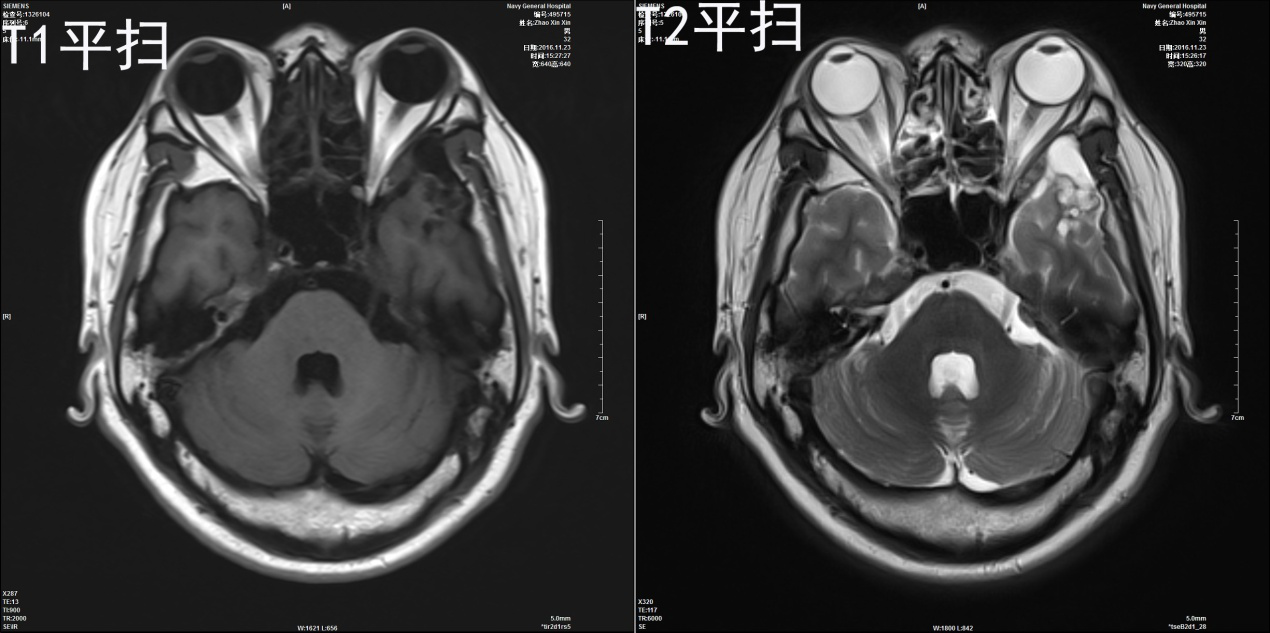

2002年11月出现意识丧失伴四肢抽搐、四肢伸直;脑电图示轻度异常;MRI示左颞叶可见长T1长T2信号,与左眼眶关系密切,强化不明显(图1)。此后开始服用卡马西平,病情反复、发作频率不规律,持续2-5分钟;2006年加服用丙戊酸钠,症状逐渐稳定,定期复查影像无明显变化,但药量逐渐增加。2016年11月入我院行“左颞叶致癫痫灶切除术”,术中显微镜下可见病变组织呈鱼肉状、质稍软,血供一般,内见囊变,完整切除肿瘤(病理号217492,部位为左颞;图2为术前影像。图3为第一次术后影像)。术后继续服用抗癫痫药物,患者于2017年2月出现左眼眶疼痛,视力下降。